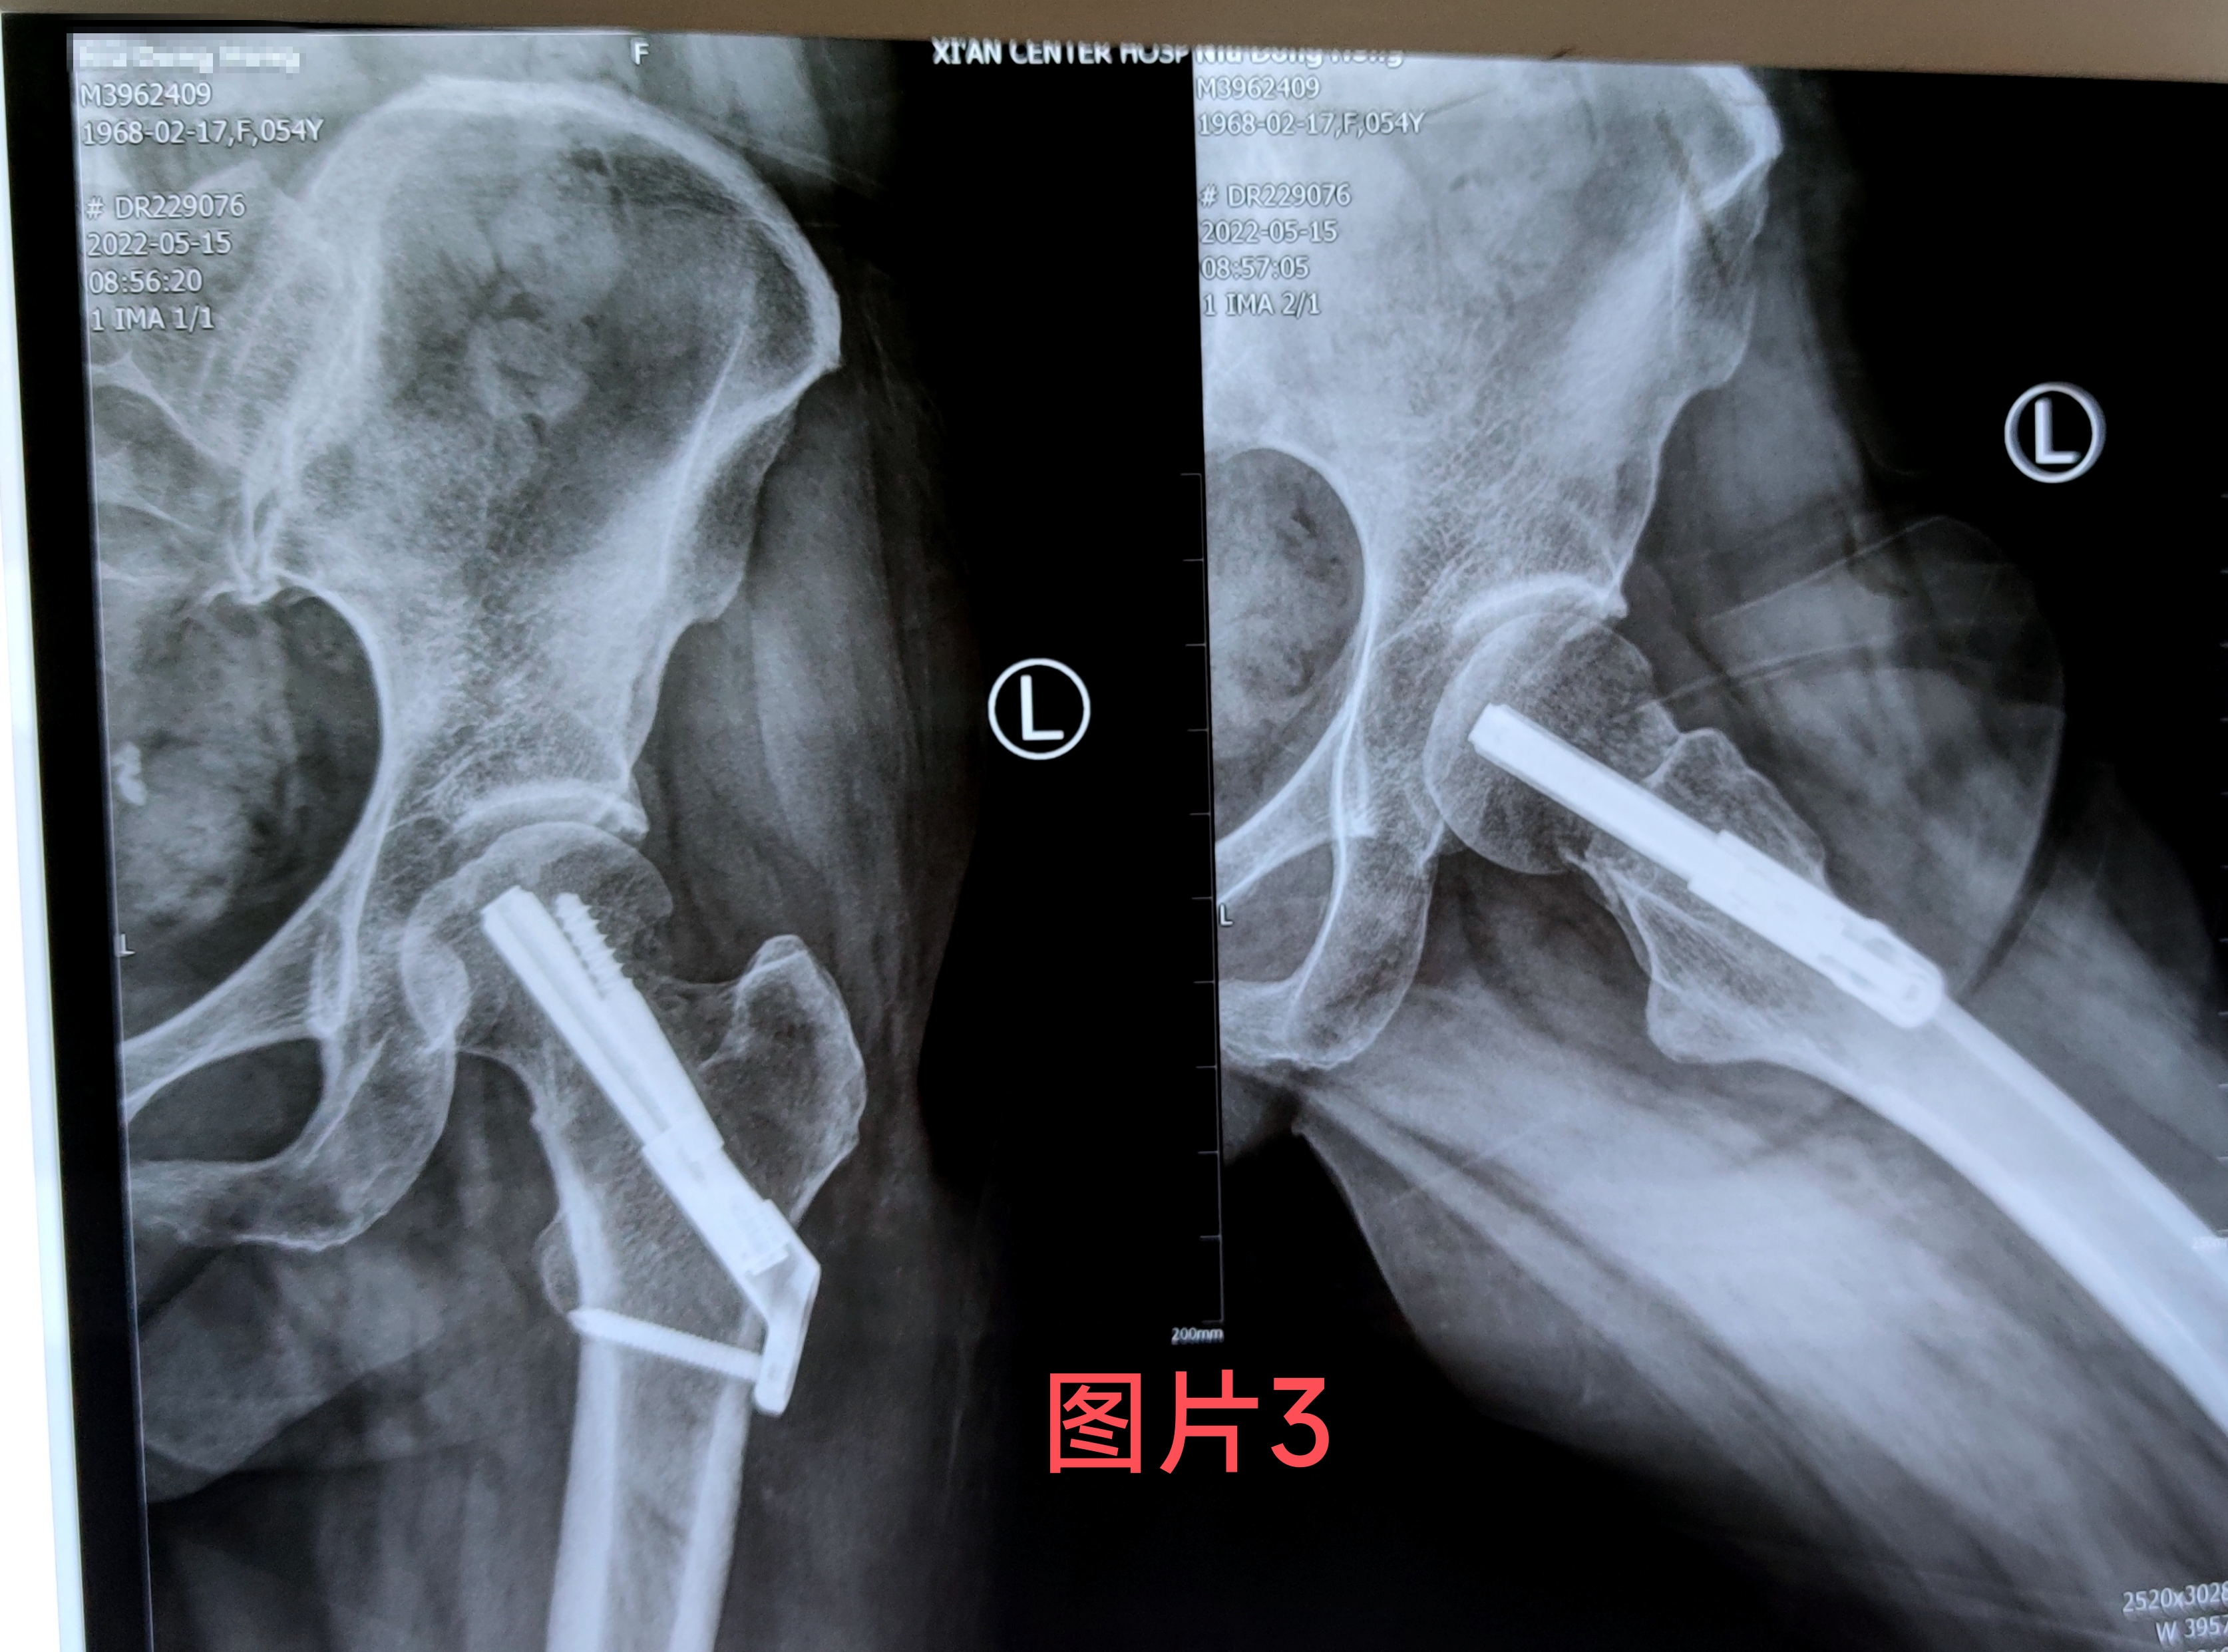

在做好相关术前准备后王涛主任医生为患者行骨折闭合复位FNS内固定手术,手术仅用半小时,手术切口3公分,手术创伤及时间比传统内固定手术大大减少,手术过程不对骨折周围血供产生干扰,最大可能地降低股骨头坏死的几率,术后当天患者无诉疼痛不适,随即开始功能锻炼。(图2)经一月复查固定牢靠,骨折无移位,无不适感(图3)。据王涛主任医生介绍股骨颈内固定系统(FNS)具有微创手术。时间短,创伤小,内固定支撑能力,防旋能力更为突出。具有力学稳定,滑动加压等优点,有利于患者早期恢复,降低股骨颈骨折不愈合发生率。王涛主任医生带领张磊卢洋主治医生治疗团队目前已为3例进行了此类手术均取得良好的手术疗效及治疗经验。填补了六合彩生肖空白。